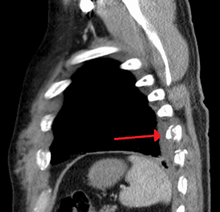

| An X ray showing multiple old fractured ribs of the person's left side as marked by the oval. | |